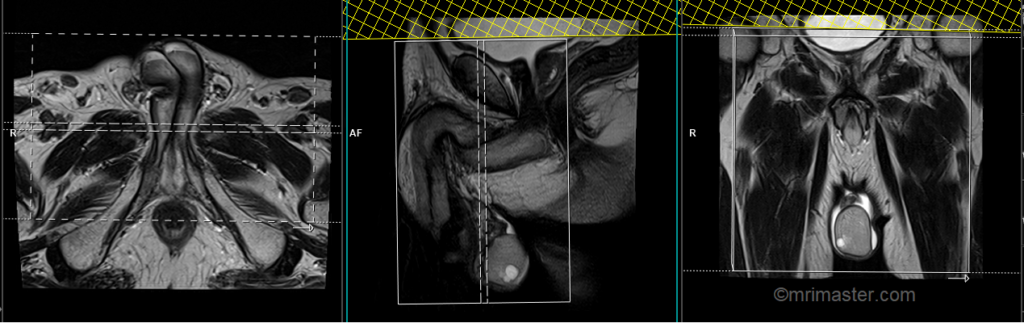

T1 tse coronal 3mm SFOV

Plan the coronal slices on the axial plane and angle the positioning block perpendicular to the penile shaft. Check the positioning block in the other two planes. An appropriate angle must be given in the sagittal plane (vertically across the scrotum). Slices must be sufficient to cover the entire scrotum from the penis to the anal canal.

Parameters

TR 400-600 | TE 15-25 | SLICE 3 MM | FLIP 140 | PHASE R>L | MATRIX 320X256 | FOV 180-200 | GAP 10% | NEX(AVRAGE) 4 |

Scrotum scans rarely require contrast-enhanced imaging. However, when contrast-enhanced imaging is necessary, T1 TSE Fat-saturated small FOV axial and coronal scans should be performed following the administration of gadolinium injection (using the same planning as described earlier).